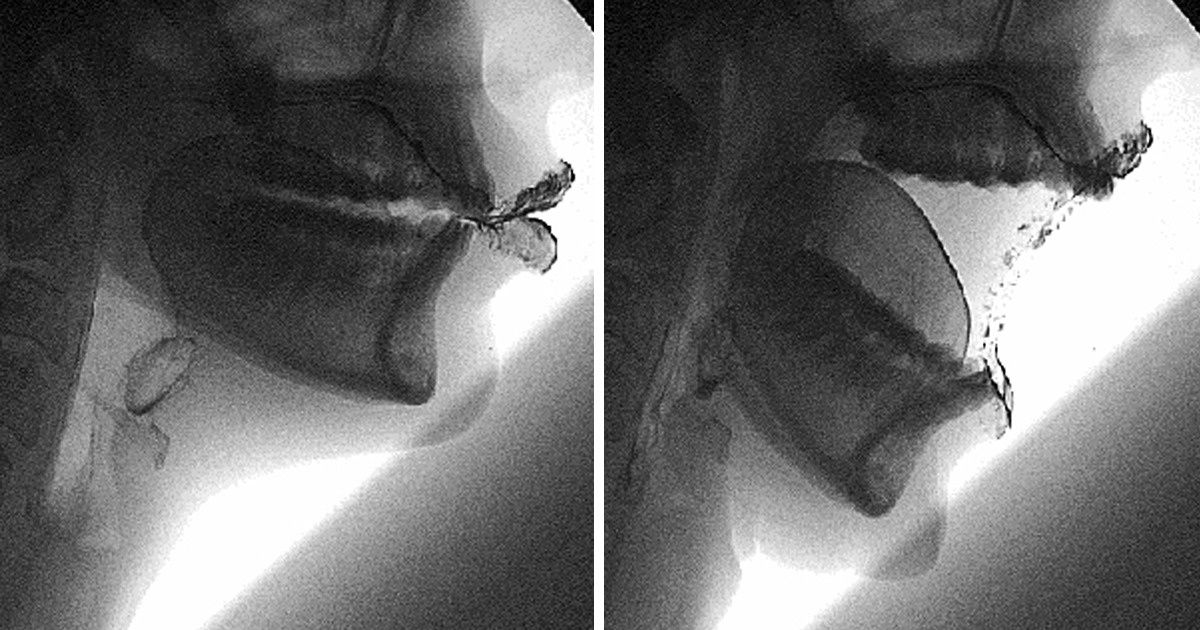

White blood cells are like an army that has different divisions fighting off threats. And it’s not only about bacteria.

In the picture, there’s a worm that is being attacked by eosinophils, white blood cells that deal with multicellular threats only, like parasites.